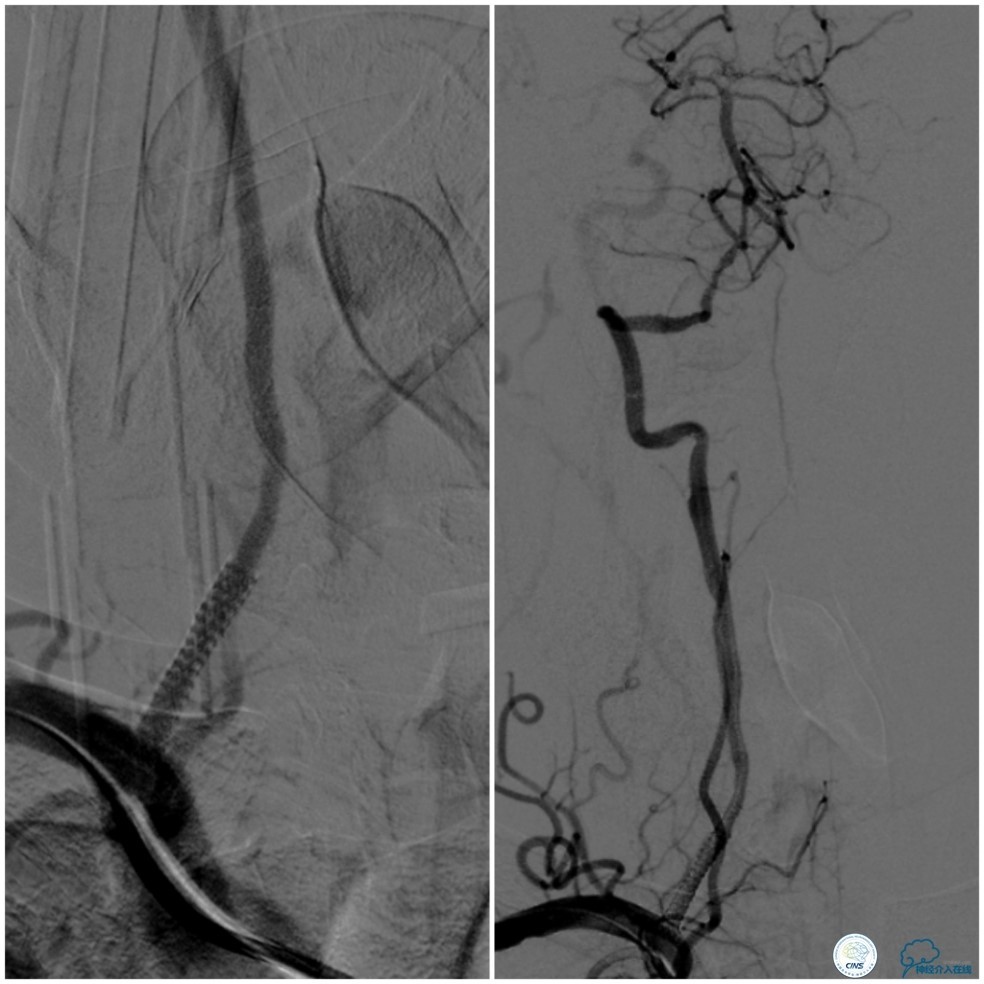

缓慢回撤6F导引导管至锁骨下动脉,造影显示右椎V1段支架无移位,前向血流正常(图17)。

图17

1. 针对后循环合并颅内外串联病变处理序贯,目前尚无统一标准,各有利弊,如考虑近端狭窄程度较重且无明显迂曲的话,可以考虑先处理近端病变(详见第14期)。

2. 本例在近端支架释放完毕后,采用球囊辅助技术顺利的将导引导管越过支架。

3. 本例右椎动脉V4段至基底动脉释放支架后,有急性原位血栓形成,这与预扩张后残余狭窄率较高有关。选用稍大直径球囊后扩张,不仅改善了狭窄率,还将新形成的小血栓机械粉碎。但在椎基底交界区后扩张要考虑有潜在血管破裂风险。